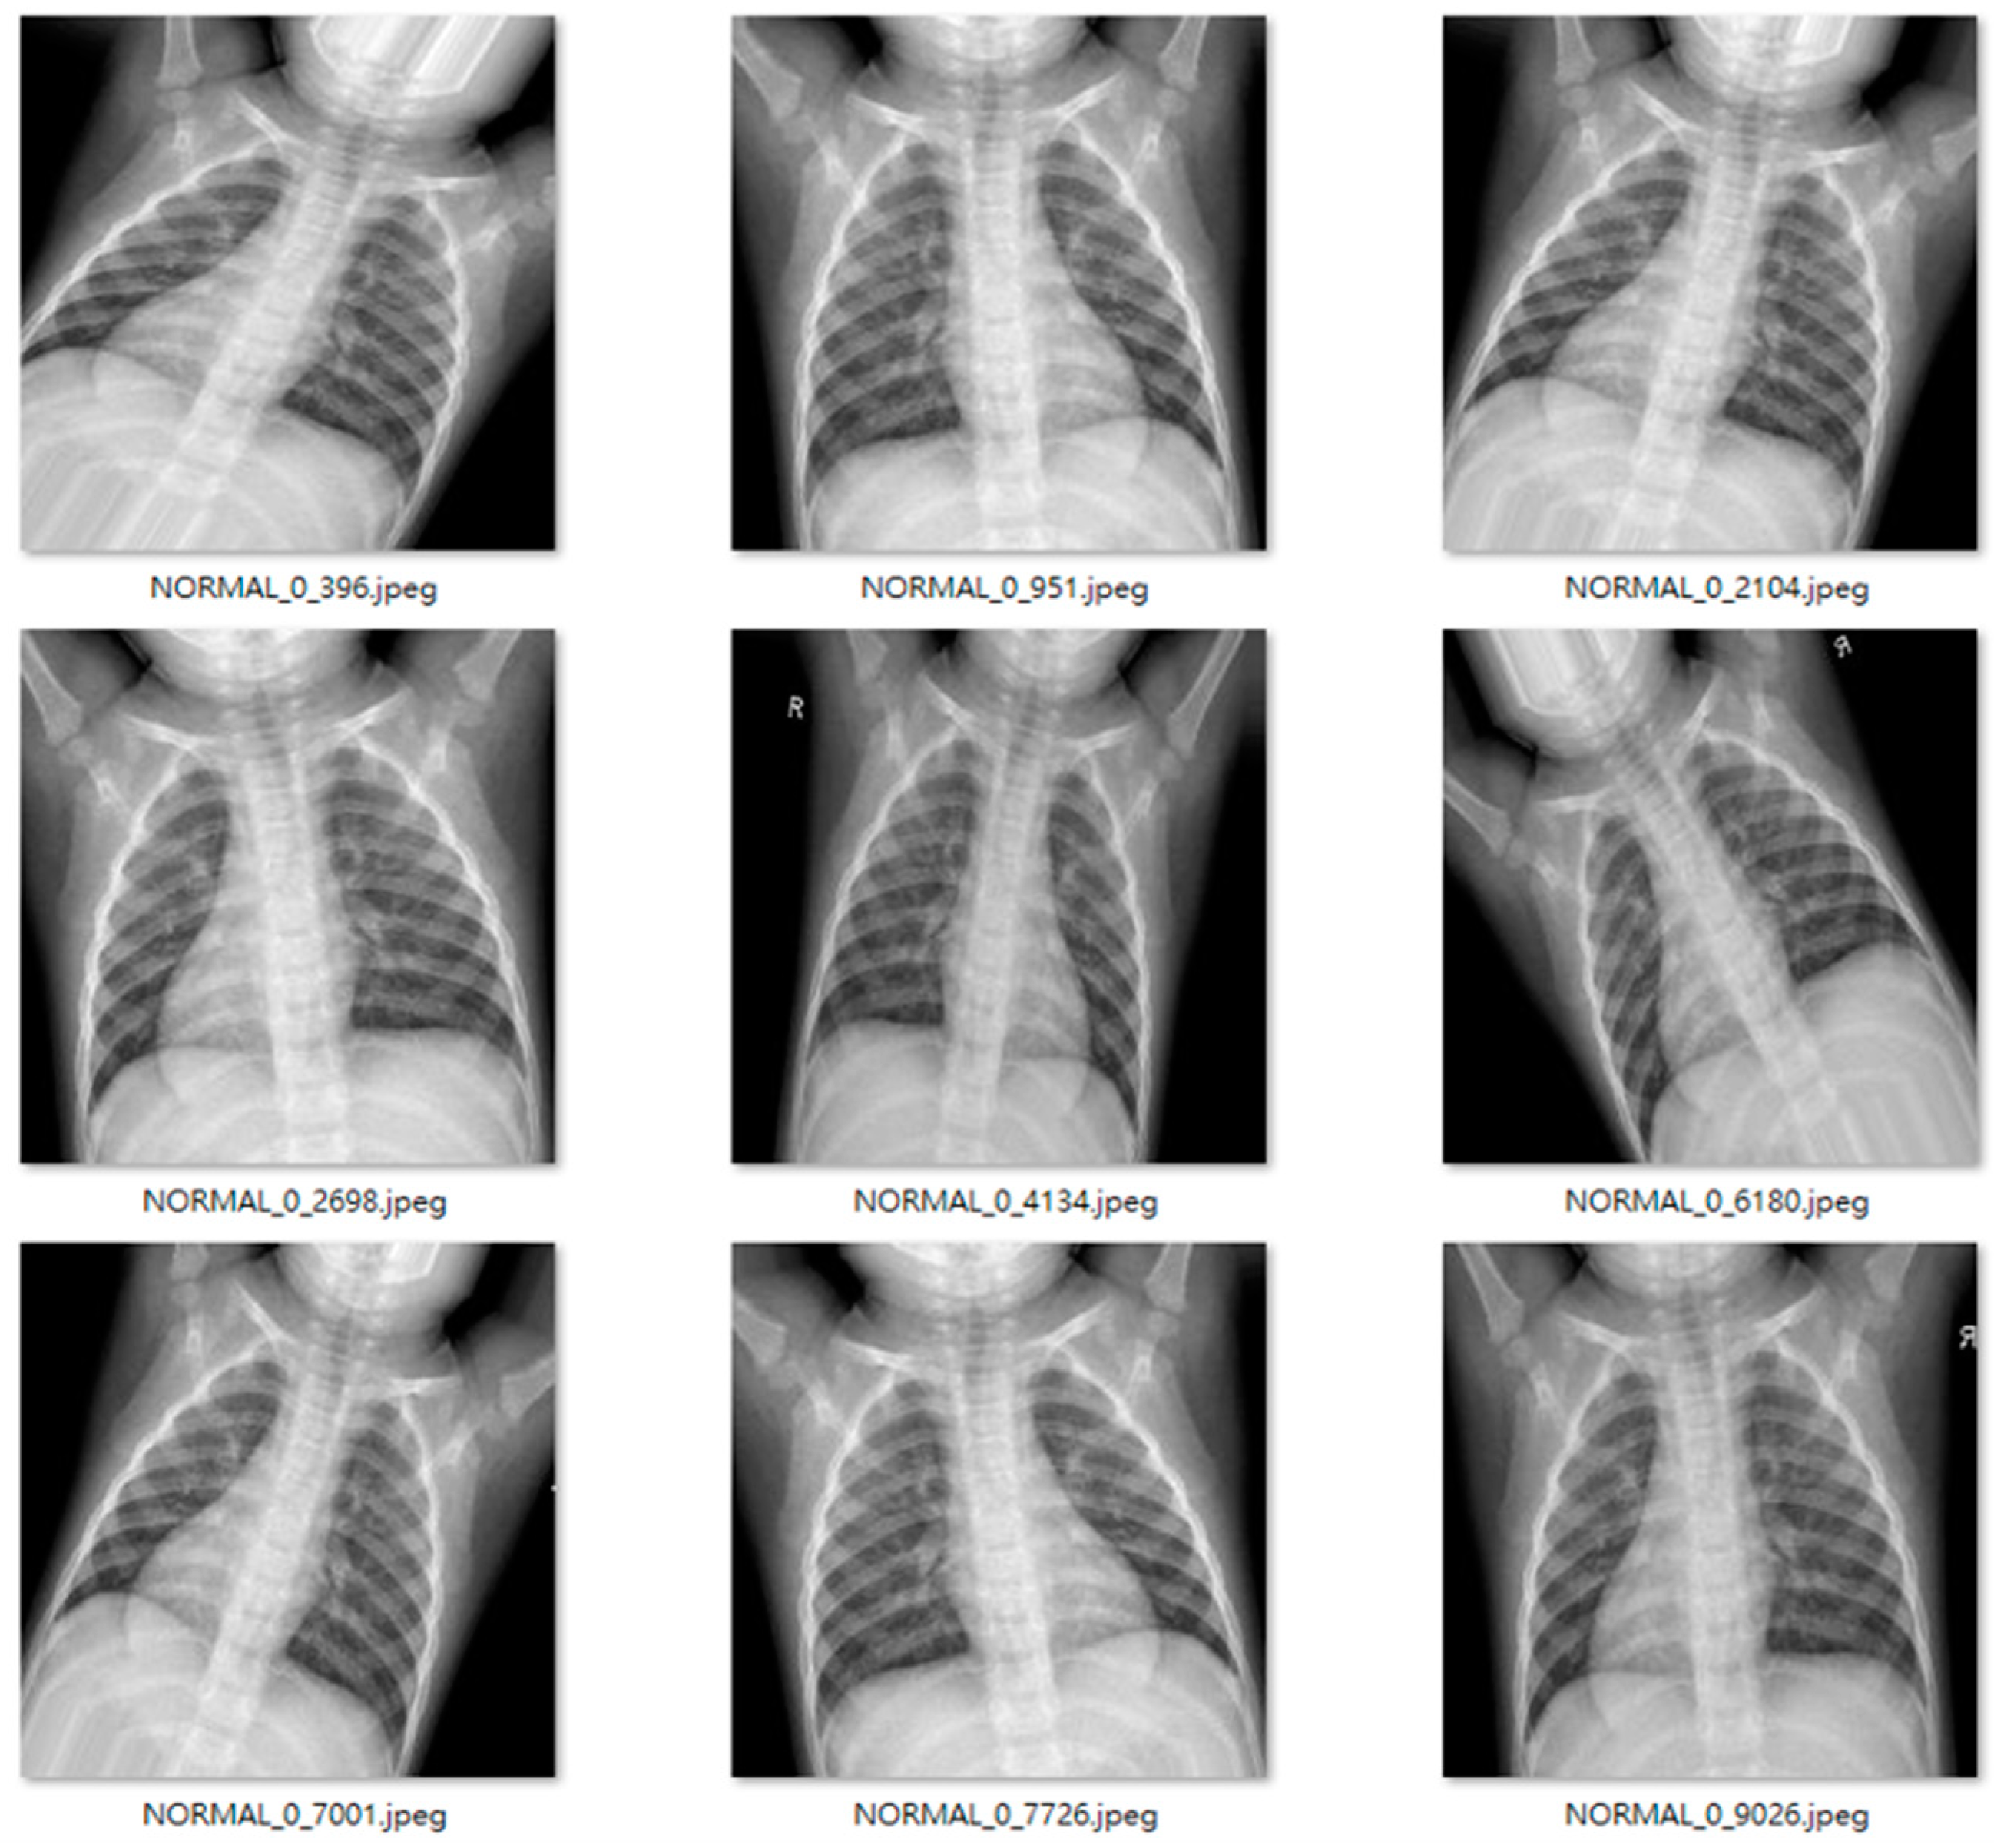

We used an open-source dataset provided by the Kaggle data science competition platform for training (https://www.kaggle.com/paultimothymooney/chest-xray-pneumonia accessed on 25 March 2018) [31]. The dataset comprised thoracic cavity images from child patients (1 to 5 years old) from the Guangzhou Women and Children’s Medical Center, China. These images were classified by two expert physicians and separated into training, test and validation sets. Figure 8 displays the dataset structure, with training sets including 1341 and 3875, test sets 234 and 390, validation set 8, and eight normal and pneumonia images, respectively. Figure 9 and Figure 10 show examples of normal and pneumonia thoracic cavity X-ray images, respectively.

Figure 10. Example pneumonia thoracic cavity X-ray images from the study dataset [31].